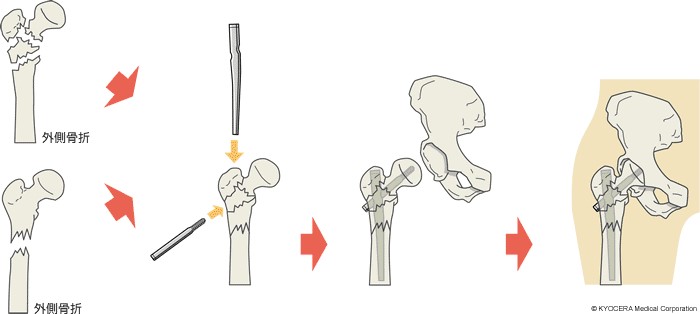

髄内釘による骨接合術 ー全テクニック公開、初心者から。MIPOの抜釘は難しい! : 整形外科医のブログ。髄内釘による骨接合術 ー全テクニック公開、初心者から。髄内釘を用いた骨接合術の全テクニックを公開し、初心者からエキスパートまで対応。- タイトル: 髄内釘による骨接合術- 著者: 山田 直彦- 対象読者: 初心者からエキスパートまで- 内容: 全テクニック公開ご覧いただきありがとうございます。膝関節 | 治療内容 | 藤田医科大学 整形外科。裁断済みです。視能訓練士セルフアセスメント 第43~48回視能訓練士国家試験問題集。【裁断済】日常診療に活かす診療ガイドラインUP-TO-DATE2024-2025。